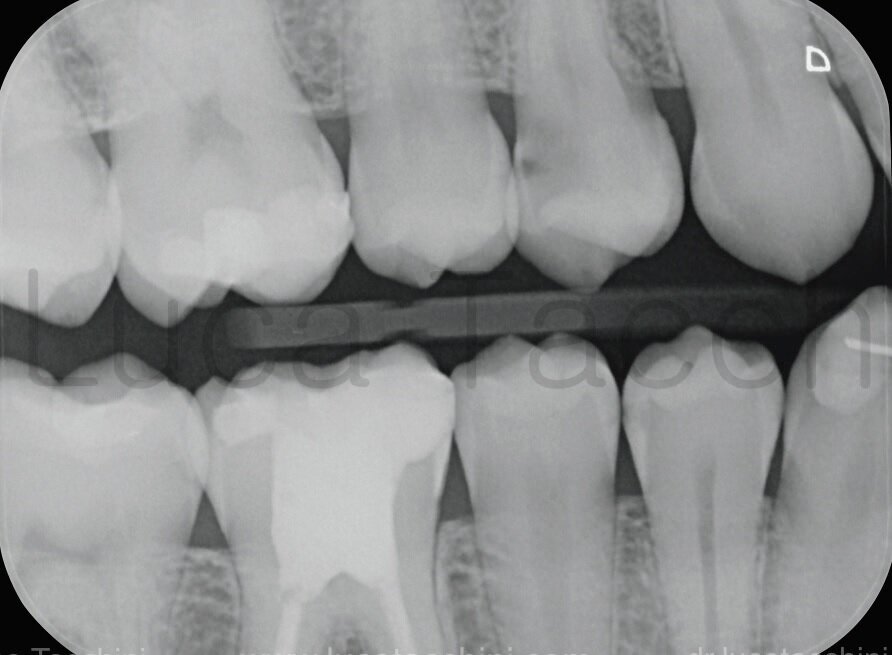

La radiografia bitewing, sempre necessaria per la diagnosi in conservativa, evidenzia anche la presenza di una lesione cariosa mesiale a carico dell’elemento 15 e di un restauro dal profilo incongruo sulla porzione mesiale dell’elemento 16 (Fig. 2).